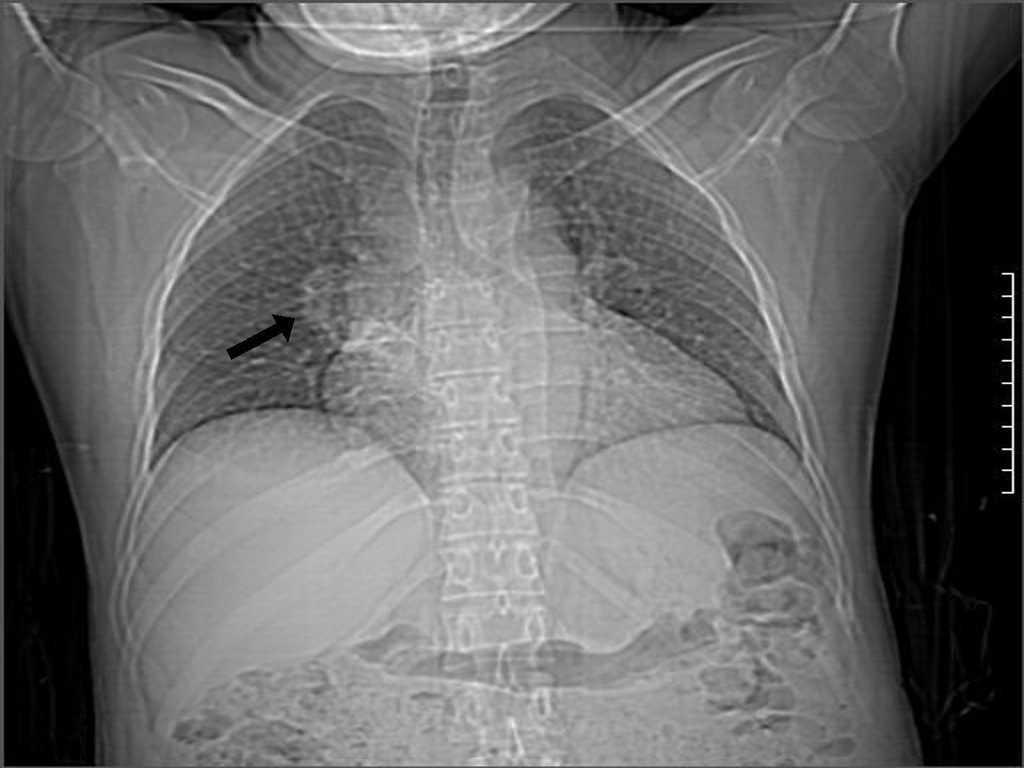

Mujer de 38 años, con trasplante renal de donante cadáver normofuncionante desde hace 3 años, tratada con prednisona, azatioprina y ciclosporina, que ingresa en nuestro servicio con cuadro de neumonía de lenta resolución y creatinina sérica de 0,9 mg/dl. En la radiografía de tórax se constata una imagen nodular en el hilio pulmonar derecho (figura 1). Se solicita una TC (figura 2) en la que se comprueba una masa sólida en el bronquio segmentario superior derecho asociada con lesiones inflamatorias del parénquima. Se realiza fibrobroncoscopia, observándose una tumoración que hace relieve endobronquial con elementos inflamatorios en su superficie. Se toma biopsia que se envía al Hospital Hermanos Ameijeiras, donde se emite el diagnóstico patológico de un seudotumor inflamatorio por Rhodococcus equi ante el hallazgo de reacción inflamatoria y la comprobación de cocos intramacrófagos, así como cuerpos de Michaelis-Gutman. Esta paciente recibió tratamiento prolongado (60 días) con meropenem y ciprofloxacino, y la imagen tumoral había desaparecido en la tomografía axial computarizada evolutiva realizada tres meses más tarde.

Figura 2. Tomografía computarizada que demuestra tumor en el bronquio segmentario superior derecho.